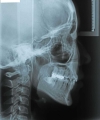

日本矯正歯科学会専門医課題症例(第4症例)

カテゴリー:ClassⅡ division 2 malocclusion (Overbite 5mm以上; 抜歯症例)

出題基準:大臼歯関係がclass Ⅱで、上顎中切歯1本を含む2本以上が舌側傾斜(U1-SN 90度以下)、犬歯関係もclass Ⅱであること。ただし、日本人では症例が少ないことを考慮して、U1-SN 100度以下のclass Ⅱ過蓋咬合も認める。抜歯・非抜歯は問わない。

出題の意味:このケースの条件は一般の人には理解しにくいところがある。通常出っ歯というと上の前歯が外に向かっていることを想像するのが普通であるが、U1-SNが90度以下というのは、上の前歯は内側に傾いていることを示している。なんで??。つまりこれは骨格性上顎前突と考えられるもので、上顎が歯並びごと全体が前へ出ていて、それだと上下の前歯があまりにも離れてしまうため、上の前歯が内側に倒れて下の前歯と何とか接触しようとしている状態と考えられる。

しかし、出題基準にも書いてあるように、このケースは欧米の白人によく見られるケースで、東洋人にはきわめて稀である。そこで類似ケースとして過蓋咬合(かがいこうごう)のケースを代替えとして認めるという配慮をしている。過蓋咬合とは非常に強く深く咬んでいる状態を言う。Overbiteとは前歯の垂直的な重なり具合を示す数値で、5mm以上だと上の前歯が下の前歯をほとんど覆い尽くしている感じになるので、前から見ると下の前歯はほとんど見えない状態になる。こういう状態が典型的な過蓋咬合である。典型的なclassⅡ,division 2のケースは過蓋咬合を合併している。